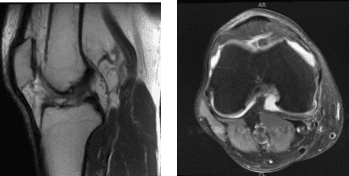

The patient presented MRI results for his left and right knees. For the right, moderate medial compartment arthrosis and a small horizontal tear along the superior articular surface of the posterior horn medial meniscus. There is evidence of previous partial medial meniscectomy.

There is mild lateral and patellofemoral arthrosis. There is a large joint effusion. For the left, Moderate-severe medial knee osteoarthritis with broad full-thickness cartilage loss and bone-on-bone apposition. Complex degeneration and tearing of the medial meniscus. Joint effusion with synovitis/debris.

MRI-3T Right knee non-contrast

MRI-3T Left knee non-contrast